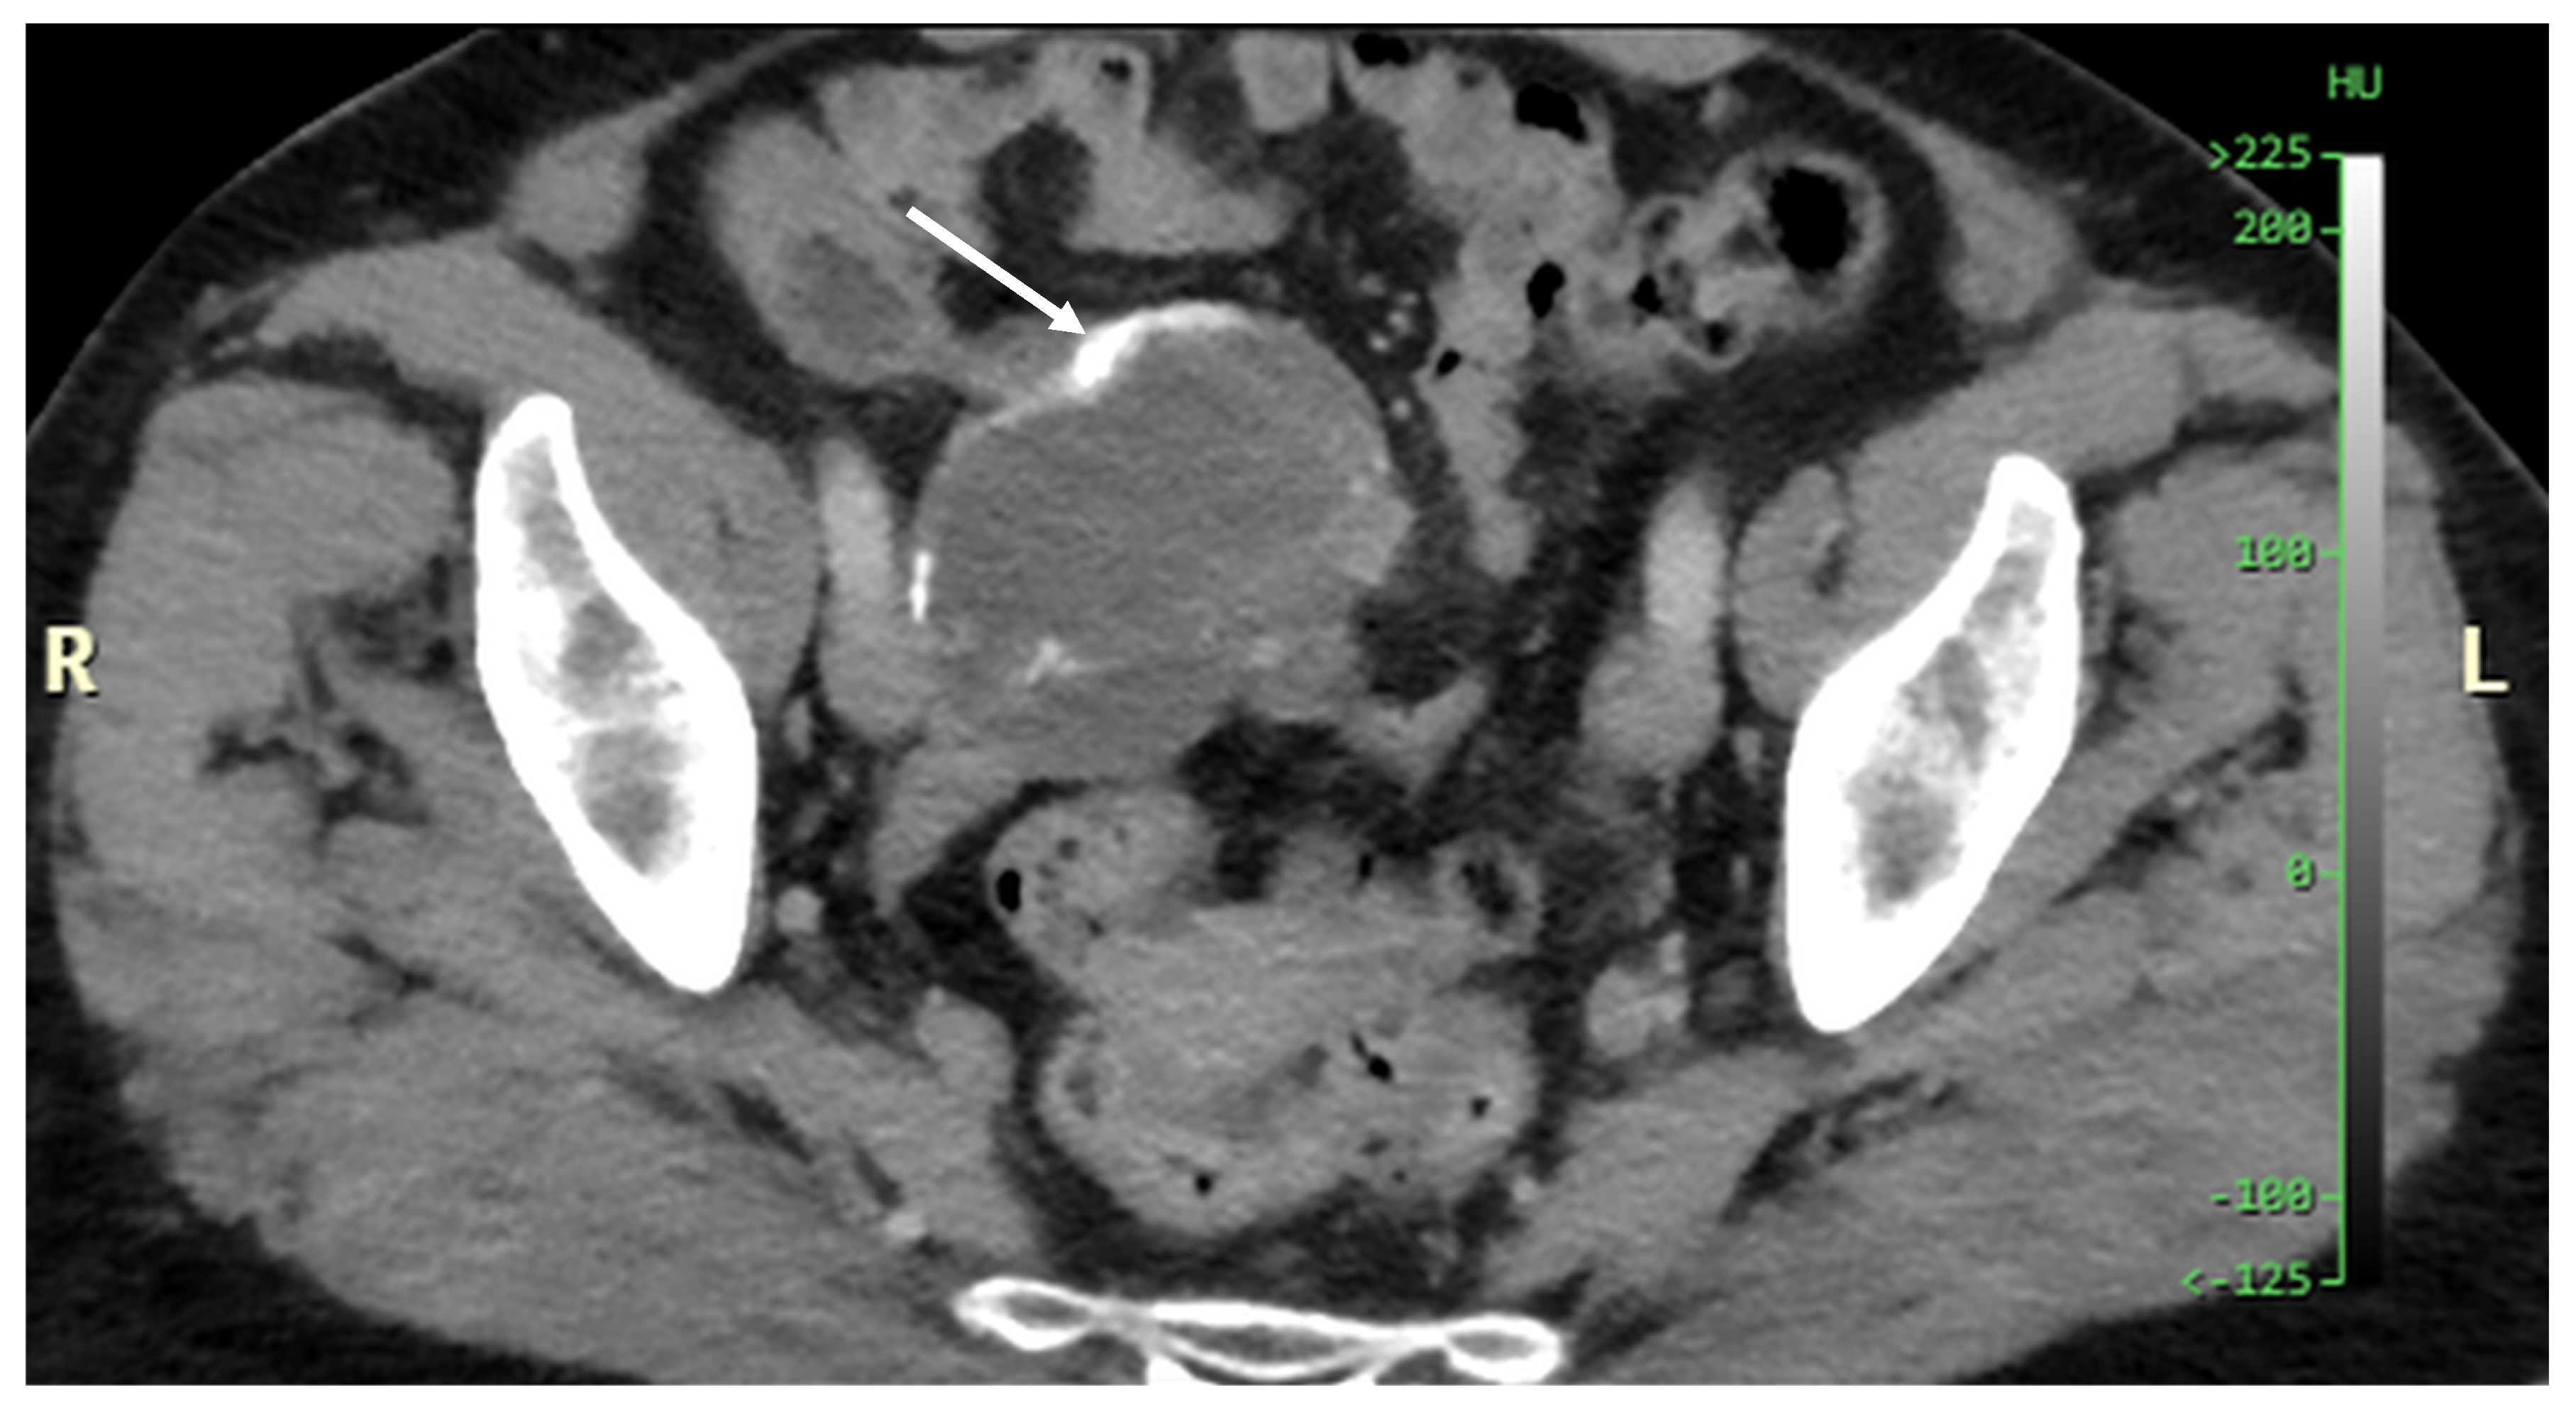

Patients with a misdiagnosed rupture of the mucocele may develop pseudomyxoma peritonei. It is characterized by the presence of an abundant gelatinous substance in the abdomen. Diffuse, progressive, and abundant mucin-containing tumor cells are typical of this disease [2] (Figure 11, Figure 12, Figure 13, Figure 14, Figure 15 and Figure 16). The interval between rupture and advanced disease is several years. In our clinical series, the interval was about 5 years. In the literature, we found a wide range of this interval from 12 months to 10 years [9,10]. The natural history of PMP revolves around the “redistribution phenomenon”, whereby mucinous tumor cells accumulate in the Douglas pouch, in the diaphragm (more on the right), and the small and large omentum (Figure 17). The small intestine is less involved [4]. Pseudomyxoma peritonei is a slowly progressing disease, which fills the peritoneal cavity over time. There are several classifications of pseudomyxoma. The most commonly used is the PSOGI classification [2]. Mucinous accumulation progresses to malnutrition, bowel obstruction, and respiratory compromise. Rarely, the tumor may spread to the pleural cavity. This has been described in 5.4% of cases. It may occur spontaneously or as a result of diaphragmatic injury during cytoreduction [8,11].

Figure 11, Figure 12, Figure 13, Figure 14 and Figure 15. Advanced stage of the disease. The abdomen is full of tumors and mucin. Typical signs are heterogeneous or hypodense masses in the form of lobules often with septa, which could be enhanced by contrast and could be associated with calcifications.

Figure 11. CT, venous phase, axial plane.